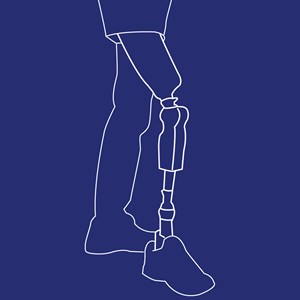

Lårbensprotese (TF protese)

Type: pdf

Størrelse: 782 KB